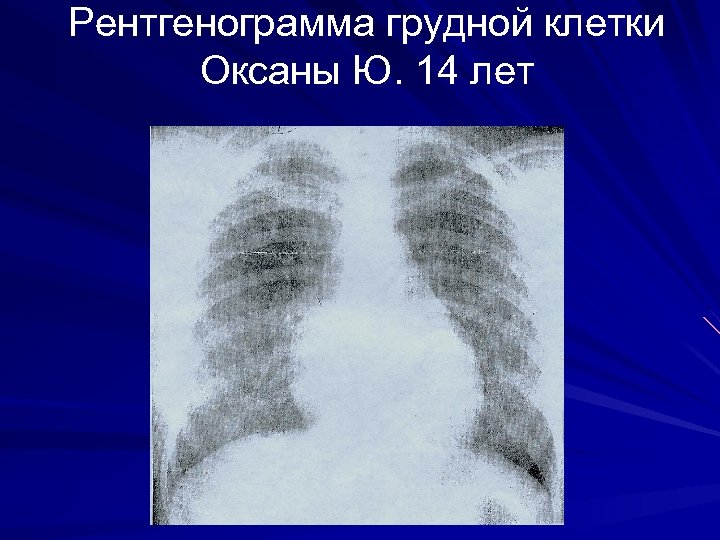

Рентгенограмма грудной клетки Оксаны Ю. 14 лет